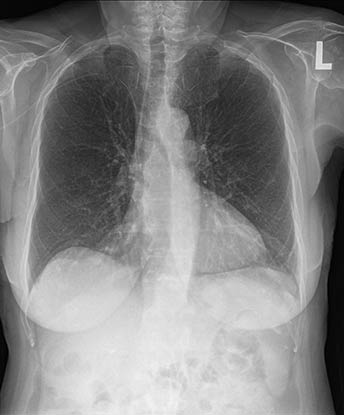

骨抑制利用人工智能创建伴随影像并抑制骨骼的出现,以增强软组织的可视化,同时不需要患者进行额外的暴露。这有助于提高病理学评估的临床信心。